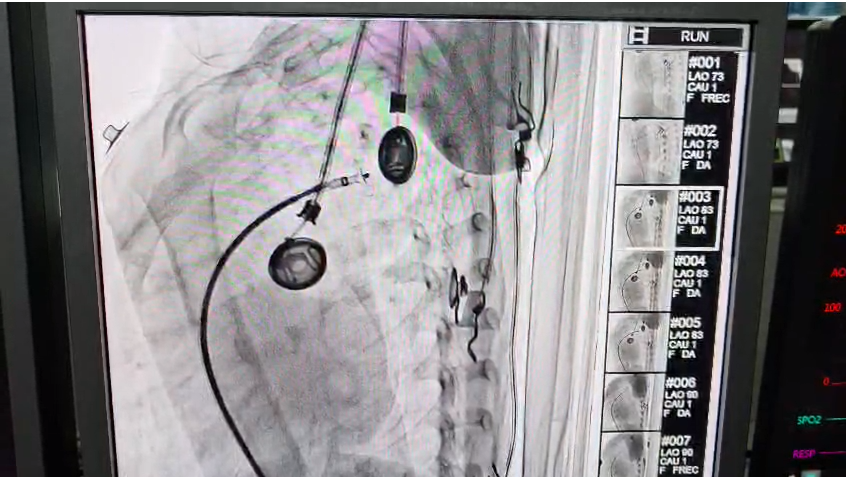

डॉ. एस.के. त्रिपाठी और उनकी समर्पित टीम ने अत्याधुनिक कैथ लैब का उपयोग करते हुए, बिना किसी बड़े चीर-फाड़ के, एक विशेष डिवाइस के जरिए हृदय के उस छेद को पूरी तरह बंद कर दिया। इस प्रक्रिया के दौरान सूक्ष्मता का विशेष ध्यान रखा गया ताकि बच्ची को भविष्य में कोई शारीरिक समस्या न हो।